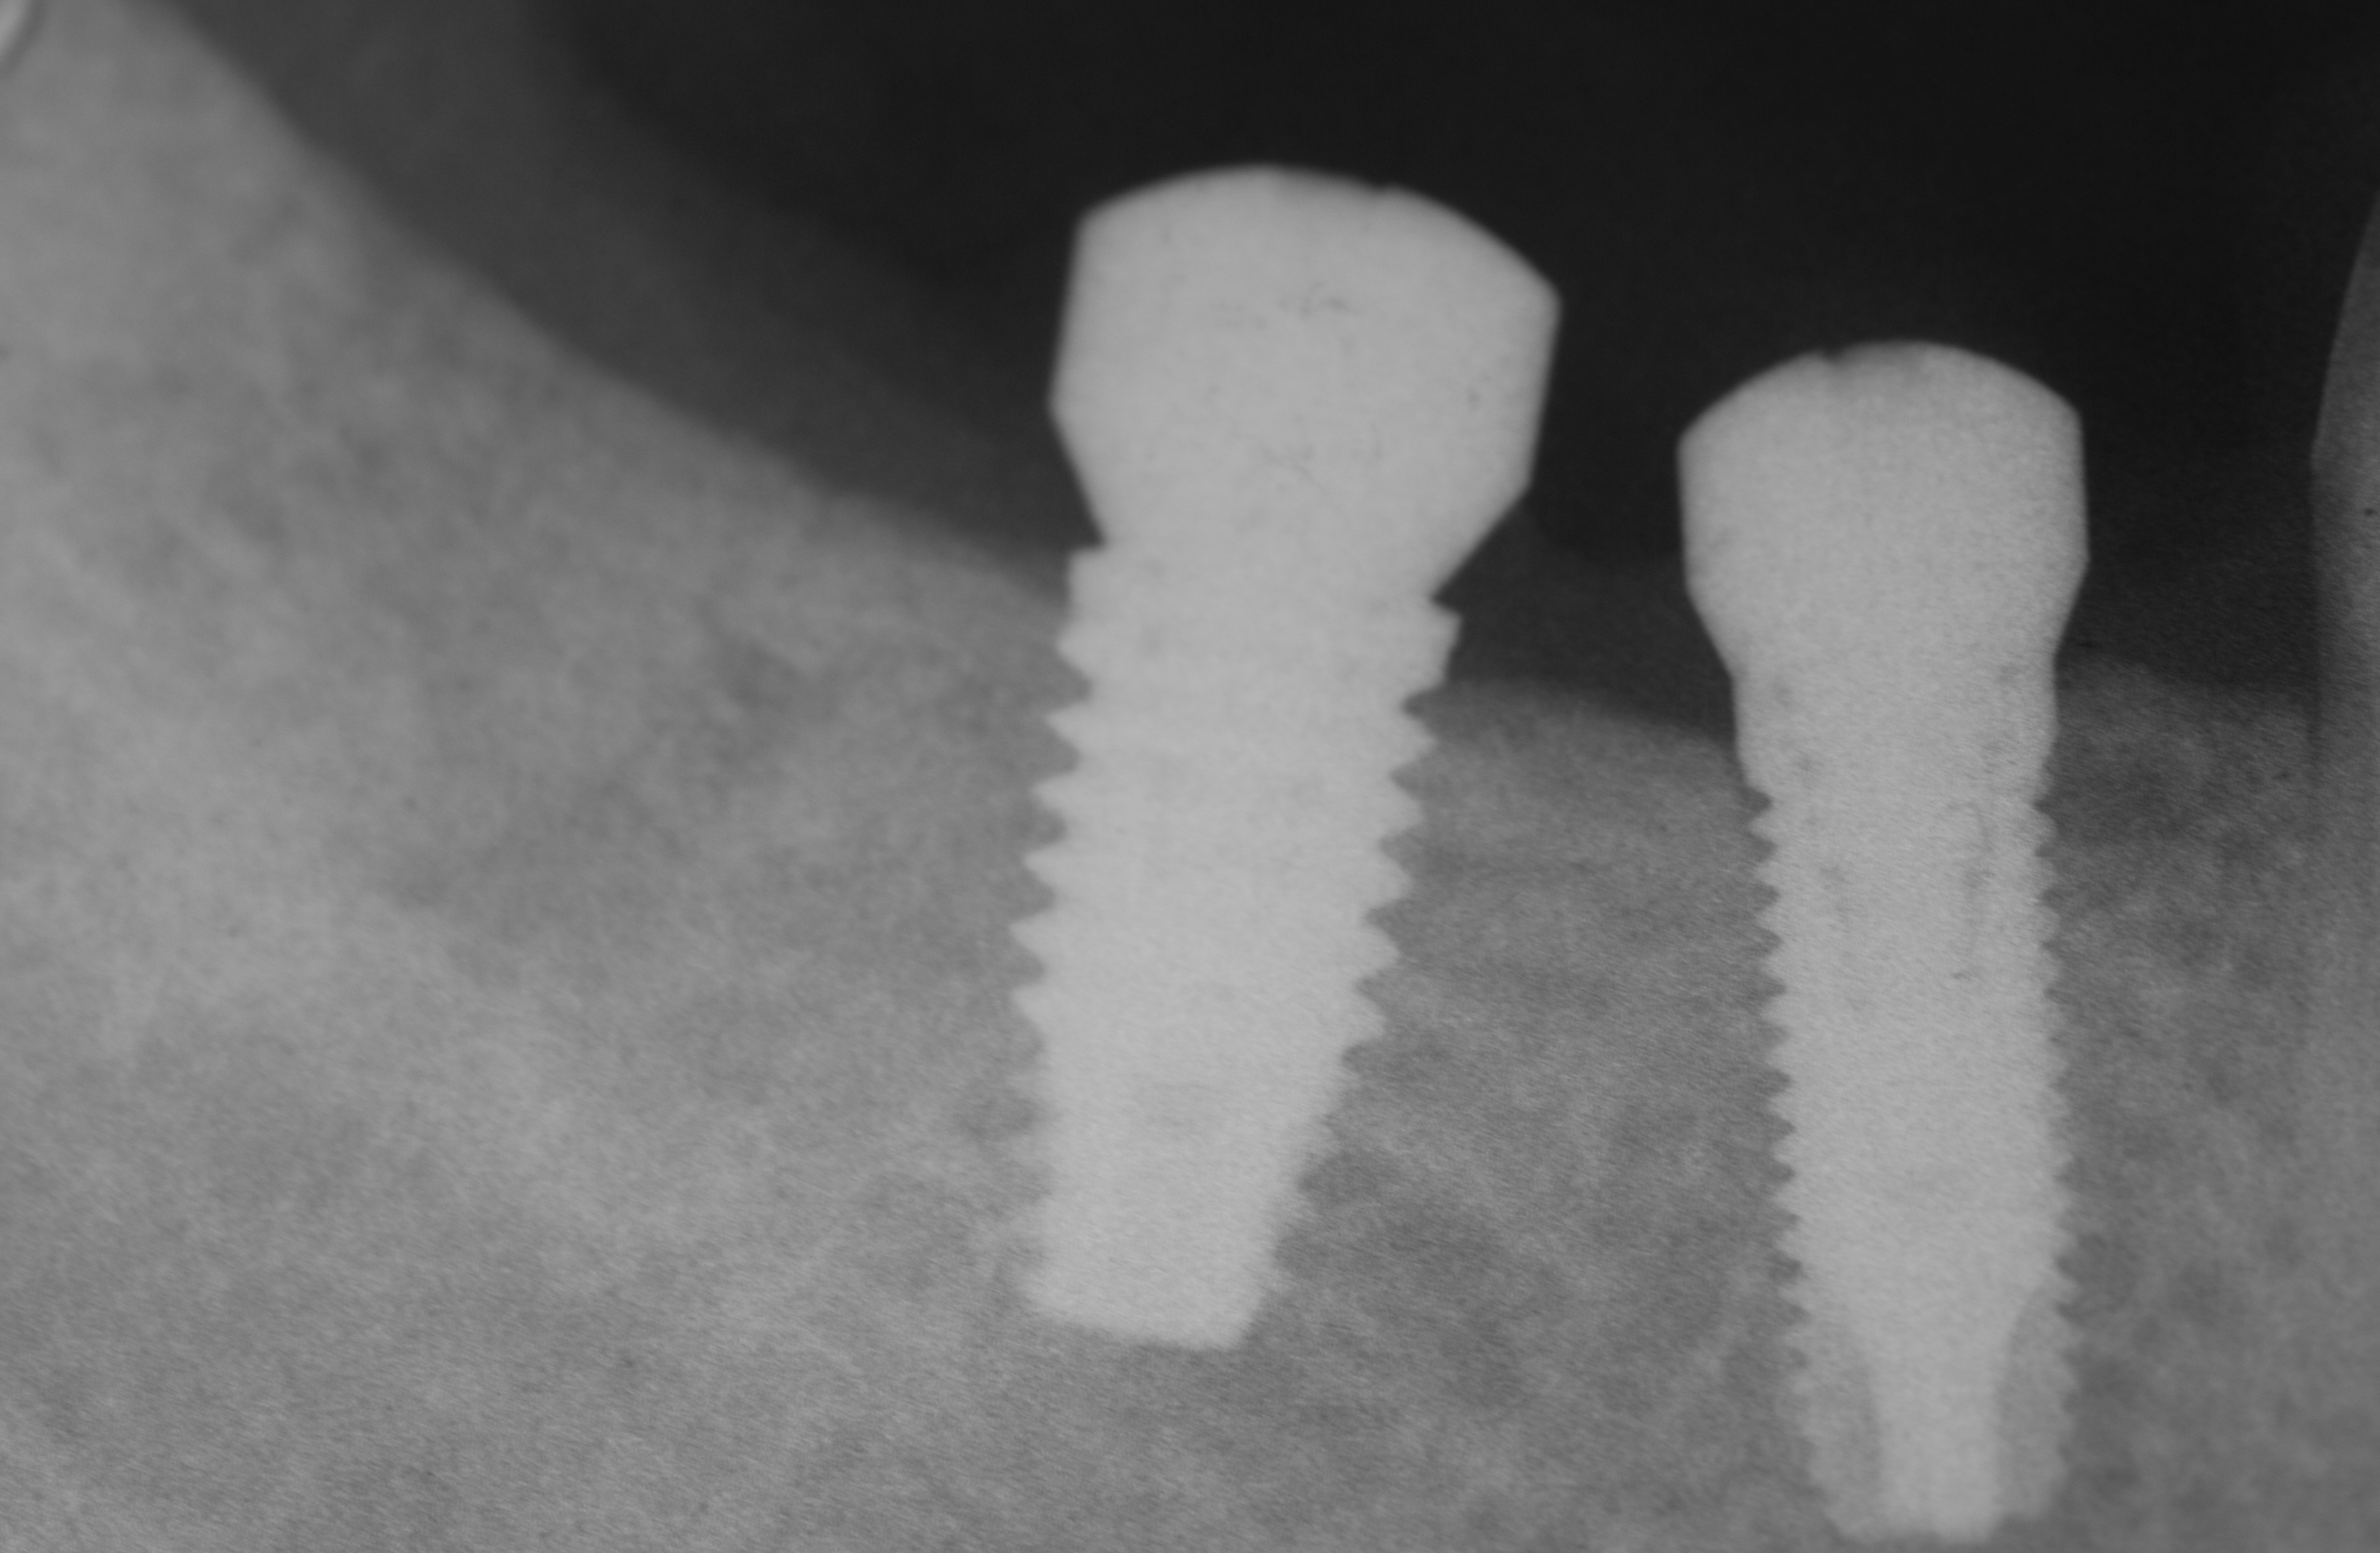

In seguito alla perdita per carie destruente degli elementi 4.5 e 4.6 si decide di riabilitare la zona interessata con due impianti. Gli impianti vengono inseriti in maniera protesicamente guidata. Si attende la completa osteointegrazione per la durata di 3 mesi dopo di che gli impianti vengono caricati prima attraverso provvisori e successivamente il lavoro viene finalizzato con elementi in ceramica.

Riabilitazione settore posteriore con impianti 3i

Sostituzione con impianti degli elementi 4.5 e 4.6